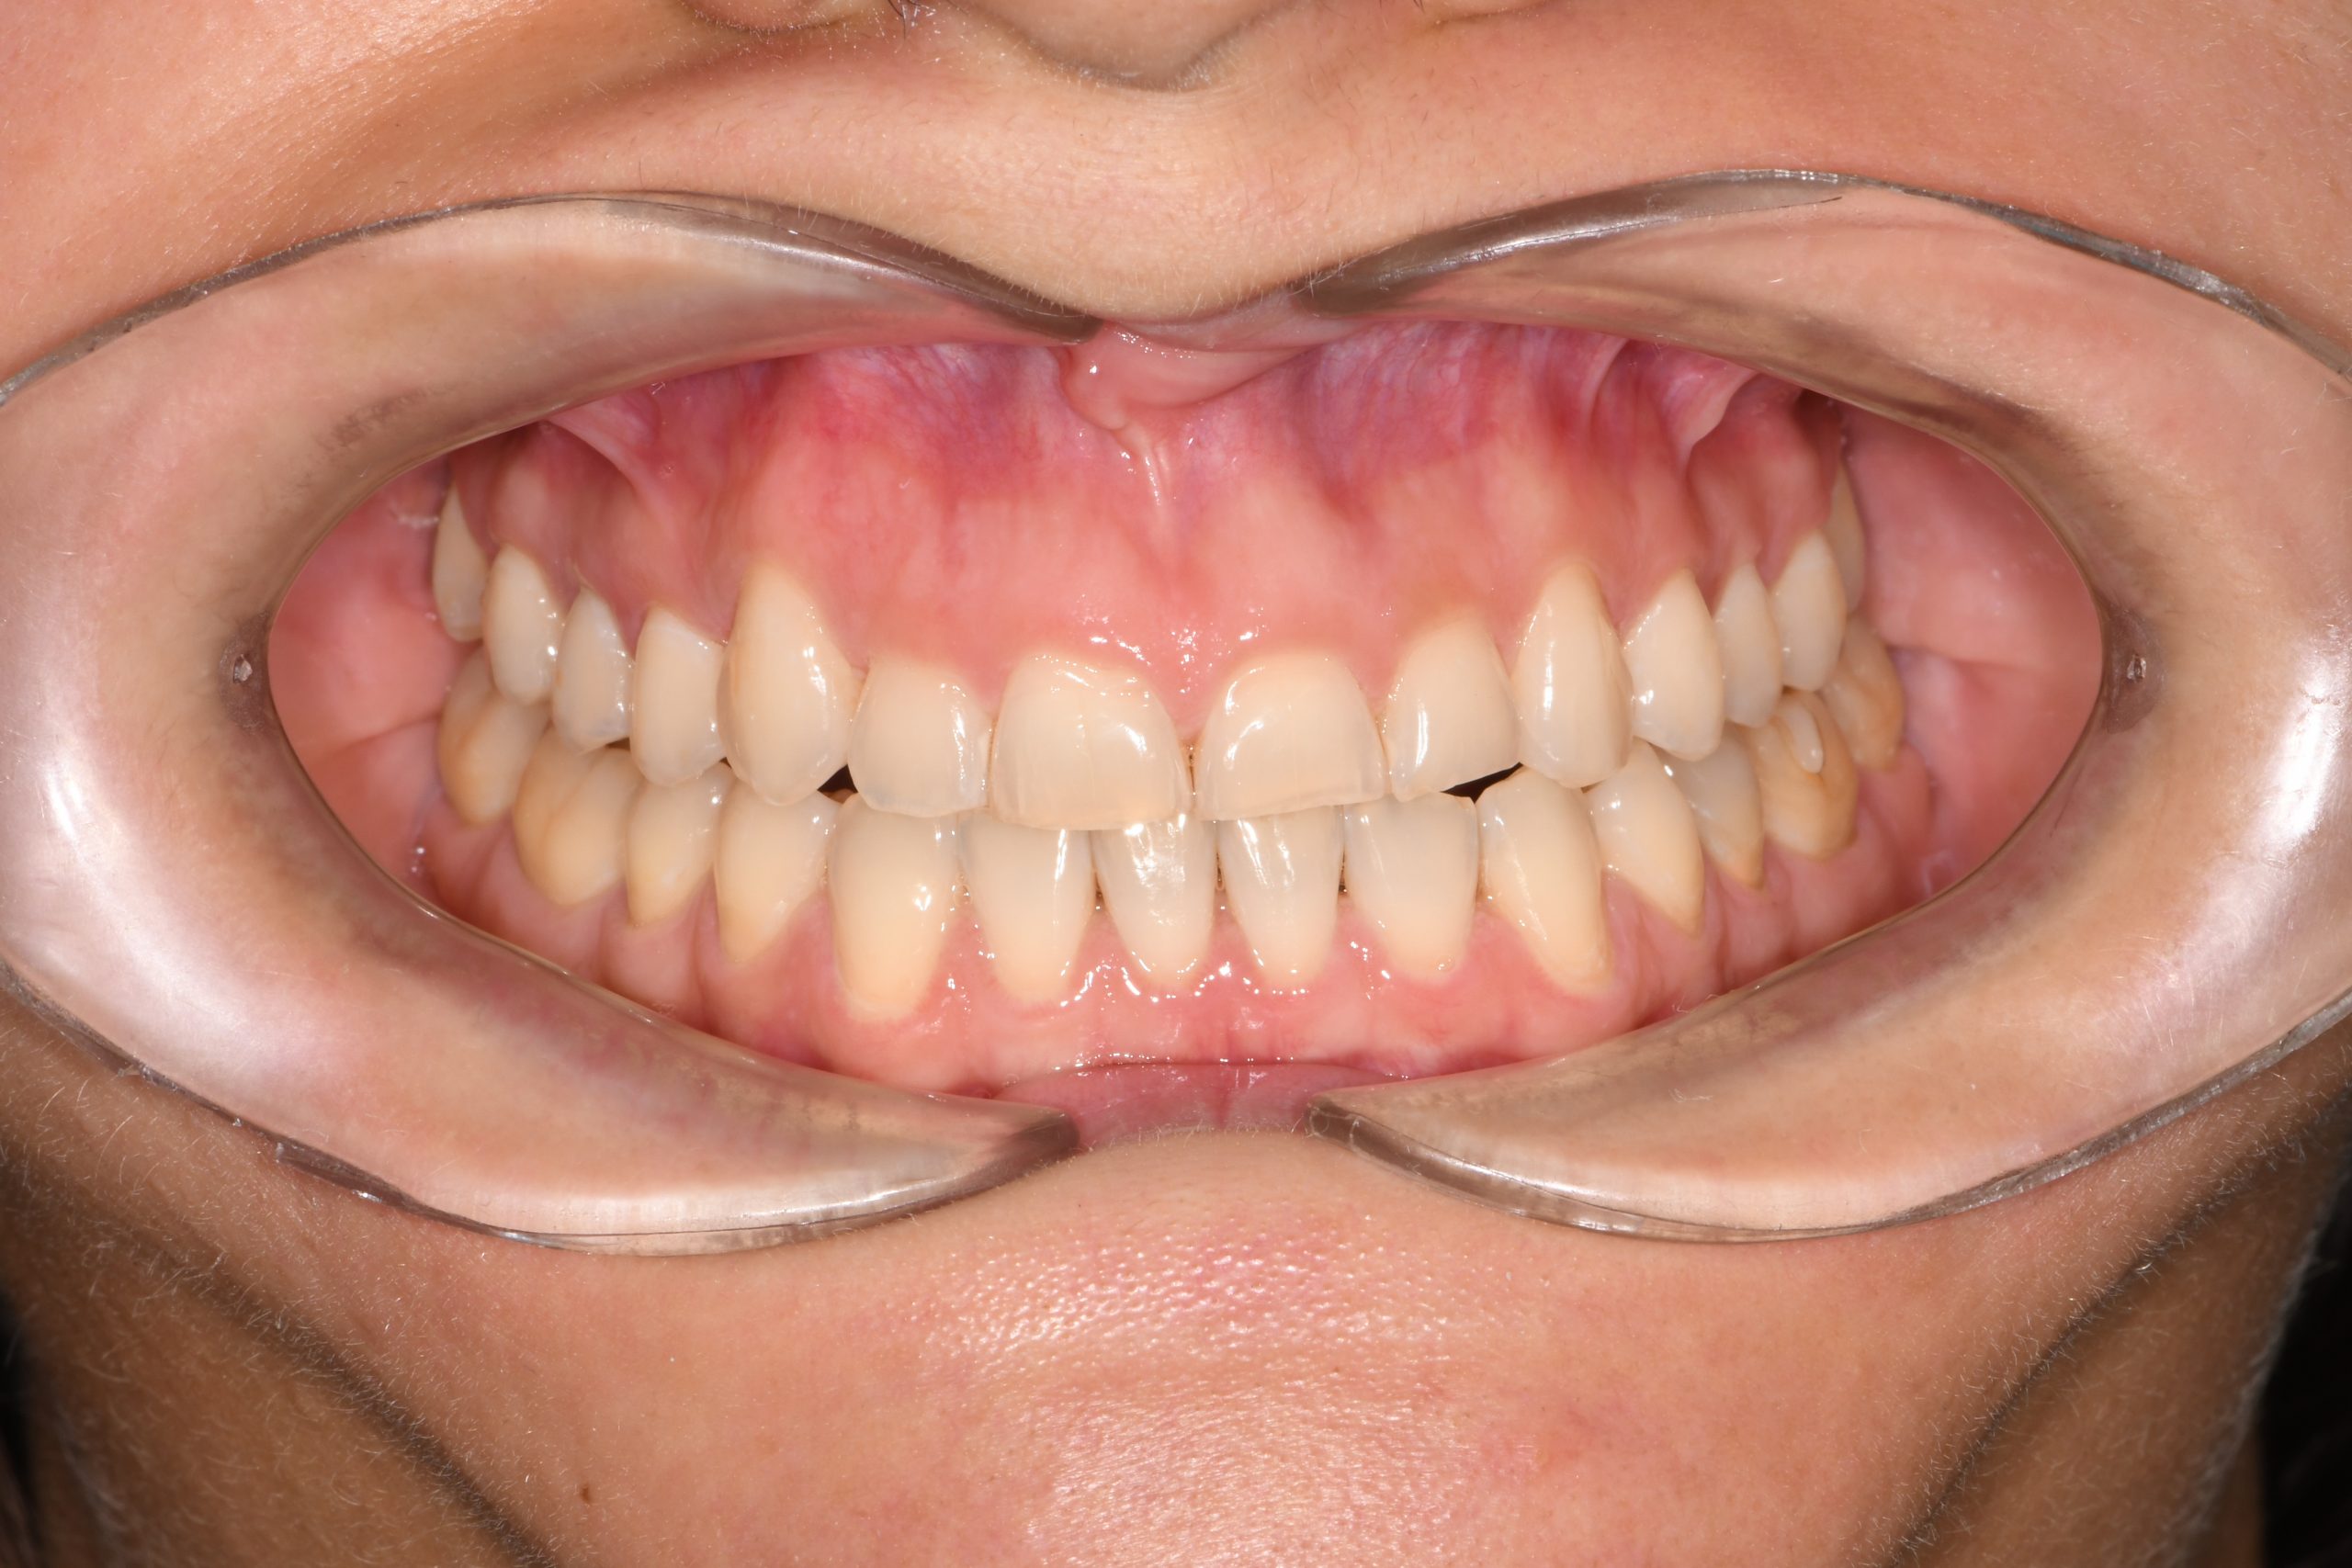

Az elmúlt évekből rengeteg szakmai referenciát tudnánk bemutatni, amelyek különböző fogszabályozási problémákat oldottak meg. Válogatva a több száz esetből, ezen az oldalon olyan képeket, információkat igyekeztünk bemutatni, amelyeknek a segítségével a jövőbeni pácienseinknek azt tudjuk üzenni: A Te fogsorod is lehet gyönyörű!

(Képeket a Pácienseink külön írásos beleegyezésével mutatjuk be!)